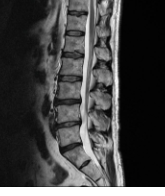

허리디스크의 치료방법은 증상의 심각도와 개인의 상황에 따라 다릅니다. 대부분의 경우에는 수술 없이 보존적인 치료로 증상을 관리할 수 있습니다. 보존적인 치료에는 다음과 같은 방법들이 있습니다.

- 안정: 허리디스크로 인한 통증을 완화하기 위해 휴식을 취합니다. 침대나 평평하고 편안한 표면에 누워야 합니다. 너무 오래 누워있지 않고, 가벼운 운동을 하는 것도 좋습니다.

- 약물: 진통제나 항염증 약물을 사용하여 통증과 염증을 줄입니다. 의사의 처방에 따라 적절한 약물을 복용해야 합니다. 약물의 부작용이나 알레르기 반응이 있을 경우 의사에게 알려야 합니다.

- 주사: 통증이 심한 경우에는 디스크가 튀어나온 부위에 스테로이드나 진통제를 주입하는 방법이 있습니다. 이는 임시적인 통증 완화를 위한 방법이며, 의사의 지시에 따라 시행해야 합니다.

- 물리치료: 전문가의 지도 아래에서 물리치료를 받습니다. 물리치료는 요법, 마사지, 전기치료, 열치료 등을 포함할 수 있습니다. 물리치료는 통증 완화, 근력 강화, 자세 개선 등을 위해 사용됩니다.

보존적인 치료로 증상이 호전되지 않거나 신경 손상이 있는 경우에는 수술적인 치료가 필요할 수 있습니다. 수술적인 치료는 디스크 조직의 일부 또는 전체를 제거하거나 디스크를 안정화시키는 것을 목표로 합니다. 수술적인 치료는 신중하게 결정하고, 의사와 상담하여 진행해야 합니다.

허리디스크의 치료방법은 개인마다 다르므로, 의사나 척추 전문가와 상담하여 적절한 치료 방법을 결정하는 것이 중요합니다. 의사의 지도를 따라 치료를 진행하고, 증상의 변화를 주기적으로 확인하고, 재발 방지를 위해 건강한 생활습관을 유지하는 것이 좋습니다.